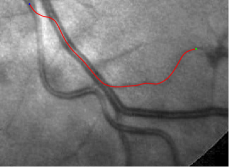

In this paper, we propose a coherence-penalized minimal path model, where the associated minimal paths favour to pass by a vessel that is located in the flatten region of an external feature map. We observe that along a piece of retinal vessel, the values of gray levels vary slowly. More specifically, retinal arteries have lower contrast of gray levels than veins due to the blood materials and imaging modality. In other words, in some extent the arteries and veins are distinguishable in terms of vesselness values. Such an observation can be used to solve the short branches problem that the minimal paths associated to a metric may pass through segments belonging to different vessels as shown in Figs. 1b and 1c. Fig. 1d shows the result from the proposed method, which can avoid such problem. Fig. 1a gives the artery-vein (AV) groundtruth. In this paper, we denote by blue and green dots the source and end points respectively.

Compare to existing minimal path models. The Riemannian metrics used in [1, 4, 5] are based on the local pointwise information. The curvature-penalized metric [7, 6] and the proposed coherence-penalized metric are able to consider more constraints, i.e., the rigidity for [7, 6] and feature coherence for our metric. These constraints are beneficial to the respective geodesics to reduce the risk of short branches combination problem. Compared to the curvature-penalized metric, our method can be more flexible since the feature map can be produced dependently on the task. In retinal imaging, veins and arteries are distinguishable in terms of gray levels or vesselness values, satisfying the formulation of the proposed model. Especially for vessels with strong tortuosity, the curvature-penalized metric, which favours a smooth curve, fails to catch the expected vessels as shown in the left column of Fig. 2. From the right column of Fig. 2, one can see that our model can obtain a good result.

Validation. We validate our minimal path model on respective 54 and 30 patches obtained from the DRIVE [14, 15] and the IOSTAR [16] datasets with AV groundtruth. Each artery involved in these parches locates near a vein or crossing it at least once. Our goal is to extract the artery between two given points. In order to get the quantitative evaluation, we first convert each continuous spatial path to an 4-connected digital path which is considered as a pixel collection. We denote by the collection of digital path pixels inside the artery groundtruth map . Thus, a measure can be simply defined as , where and mean the respective number of elements involved in and . We compare our model to four existing minimal path models: the isotropic Riemannian (IR) model [1], the anisotropic radius-lifted Riemannian (ArR) model [4], the isotropic orientation-lifted Riemannian (IoR) model [5] and the curvature-penalized (CuP) model [7]. The construction of these metrics are based on the OOF outputs [12]. Note that a centerline-based potential is chosen so that we remove the radius dimension of [5] to reduce computation complexity. The results in terms of the score are presented in Table 1, including the average (Avg.), maximum (Max.), minimum (Min.) and standard deviation (Std.) values. In both DRIVE and IOSTAR datasets, our method can achieve the best performances thanks to the coherence penalization. Note that in Table 1, we evaluate our method by using the refined paths instead of using the original coherence-penalized minimal paths. For comparisons in visualization, we show the minimal paths from the ArR metric , the CuP metric and the proposed coherence-penalized metric on three retinal patches as shown in Fig. 3. The targeted artery vessels which cross veins at least once are labeled by red color in column 1. The paths shown in column 4 from the proposed metric are results after refinement. One can claim that our method indeed can catch expected arteries while other metrics fall into the traps of short branches combination.